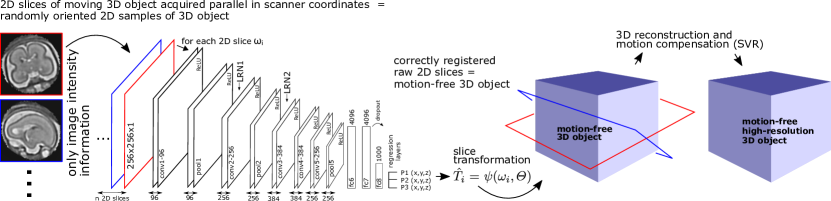

The core of our method utilises a CNN, called SVRNet, to regress and predict transformation parameters , such that , where is the learned network parameters and are a series of 2D image slices that are acquired from a moving 3D object . SVRNet provides a robust initialisation for intensity-based registration refinement by predicting for each (see Fig. 1). We also define as known ground truth parameters of during validation.

Our proposed pipeline consists of three modular components: (I) approximate organ localisation, (II) prediction of , and (III) 3D reconstruction/ intensity-based registration refinement.

Organ localisation, which defines a Region of Interest (ROI), can be achieved using rough manual delineation, organ focused scan sequences or automatic methods, such as [10] for example for the fetal MRI use case. For 3D Reconstruction, we use a modified Slice-to-Volume Reconstruction (SVR) method [8] and initialise it with transformed using . Here on, we focus on the novel part of this pipeline, which is SVRNet. SVRNet needs to be trained accurately on a desired ROI, imaging modality, and use-case scenario.

Network Design: SVRNet is derived from the CaffeNet [7] architecture. Experimentation with other architectures has revealed that this approach yields a maximum training performance whilst keeping the training effort feasible. For regression, we define multiple loss outputs; one for each . SVRNet employs therefore a multi-loss framework, which avoids over-fitting to one particular single loss [16]. Fig. 1 shows the details of the SVRNet architecture.